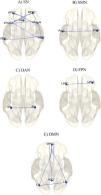

Evaluation of functional brain damage using resting-state functional magnetic resonance imaging in patients with diffuse axonal injury admitted to the ICU

Table 1. Group differences in functional connectivity within major networks. Reported statistics include the t-value with degrees of freedom [T(df)], uncorrected p-values (p-unc), and false discovery rate (FDR) corrected two-sided p-values (p-FDR, 2-sided).